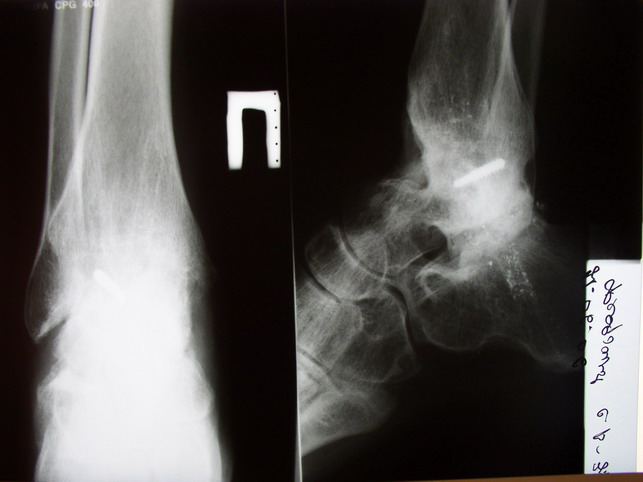

Среди повреждений таранной кости (Hawkins III-IV) с одновременной травмой лодыжек встретилось следующее (см. вложение). Пациент упал в колодец на глубину 10 метров (Х.2002 г.), госпитализирован с диагнозом: з/перелом шейки правой таранной кости (Hawkins IV) с переломовывихом тела назад и кнутри, закрытый перелом внутренней лодыжки и переднего края большеберцовой кости. Оперирован в первые 12 часов после травмы, выполнена открытая репозиция таранной кости, внутренним и передне-внутренними доступами, остеосинтез переломов шейки и тела губчатыми винтами, для реваскуляризации тела таранной кости первичный компрессионный над- и подтаранный артродез. Синтез внутренней лодыжки губчатым винтом. Удаление винтов через 1 год,2 мес. Получен анкилоз указанных суставов с сохранением длины конечности, полная реваскуляризация таранной кости, о чем говорит сращение ее переломов, отсутствие отеков и

цианоза стопы и голени. Компенсаторная подвижность переднего и среднего отделов стопы около 15-20 градусов за счет поперечного (Шопара) сустава стопы. Считаю оправданной подобную тактику, не смотря на угрожаемый прогноз (100% асептический некроз) по классифицкации Hawkins.